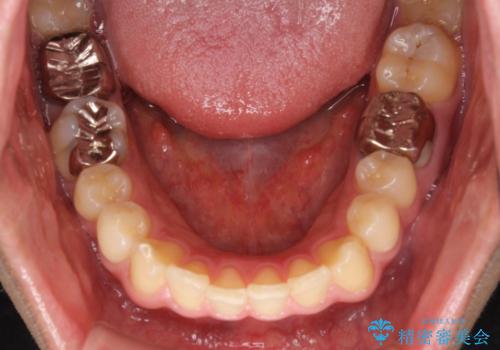

- 治療中の前歯と口腔内にある銀歯が気になるとのことで来院された患者様です。

土台に含まれている金属も含め、口腔内の金属は全て除去し、根管治療が必要な歯は根管治療を行い、オールセラミッククラウンやセラミックインレーにて治療することとしました。